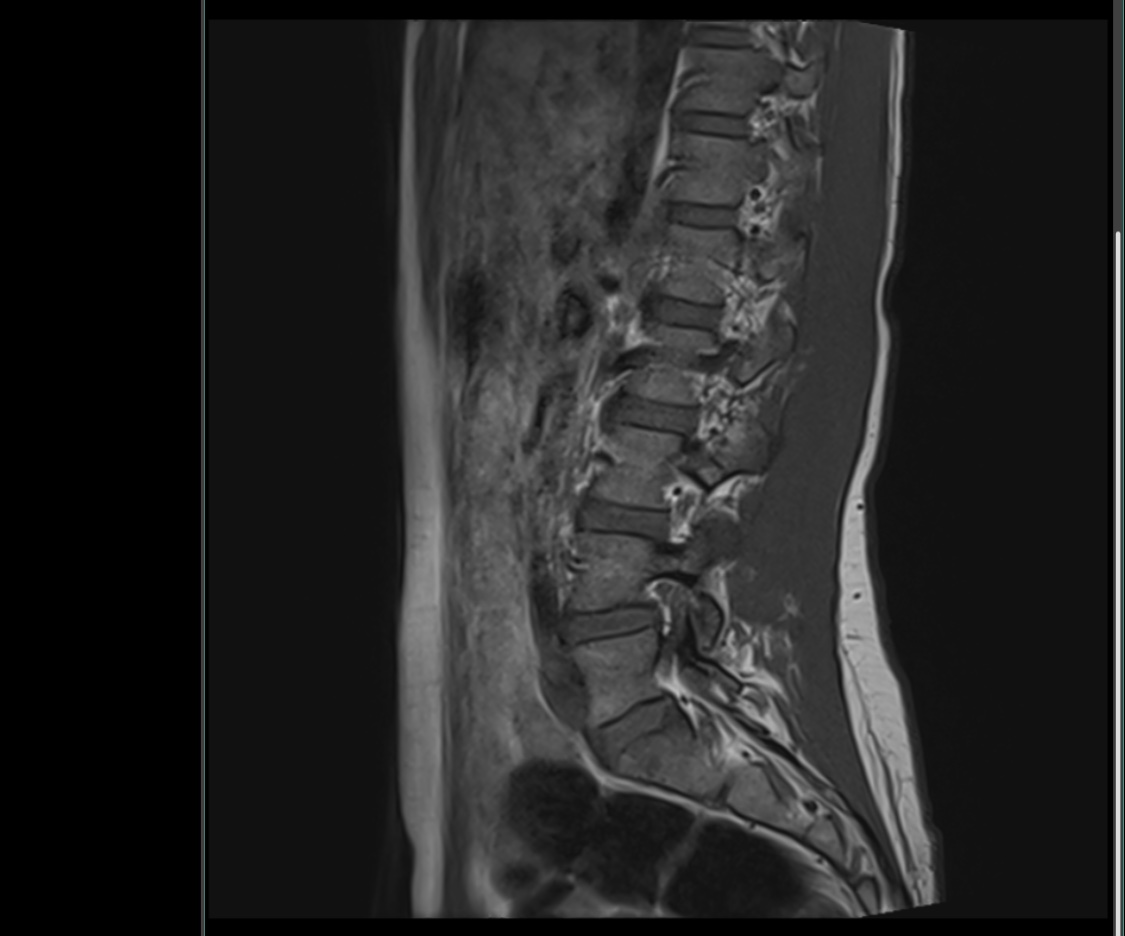

Sofand Skrevet 9. mars 2019 Skrevet 9. mars 2019 Er det noen innenfor faget som ser hva dette MR bildet av ryggen viser?

Skandinav Skrevet 10. mars 2019 Skrevet 10. mars 2019 Bildet er ikke det tydeligste, men ser ut som en gammel prolaps mellom L4 og L5.

Sofand Skrevet 10. mars 2019 Forfatter Skrevet 10. mars 2019 Bildet er ikke det tydeligste, men ser ut som en gammel prolaps mellom L4 og L5. Tusen takk for svar! Sier disse bildene noe mer kanskje?